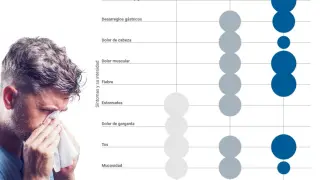

La mialgia, uno de los efectos secundarios más comunes de la vacuna frente a la covid

En el último informe de Farmacovigilancia sobre las vacunas frente al coronavirus trajo novedades en cuanto a efectos secundarios de su inoculación. En concreto, la mialgia es el tercer acontecimiento adverso más común tanto de la vacuna de Pfizer (6.604 casos con Comirnaty Original y 14 en Comirnaty bivalente) como de la de Moderna (3.366 casos con Spikevax Original) por detrás de la pirexia y la cefalea. En cambio, con Spikevax bivalente ocupa el cuarto lugar con 14 casos. En cuanto a la tercera dosis de la vacuna, la mialgia ocupa el cuarto lugar por detrás de la pirexia, la linfadenopatía y la cefalea.